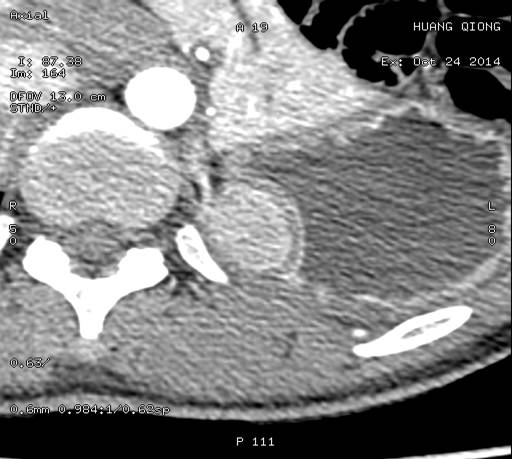

食道及周边结构(气管分叉层面 A:CT 扫描;B:小探头超声)